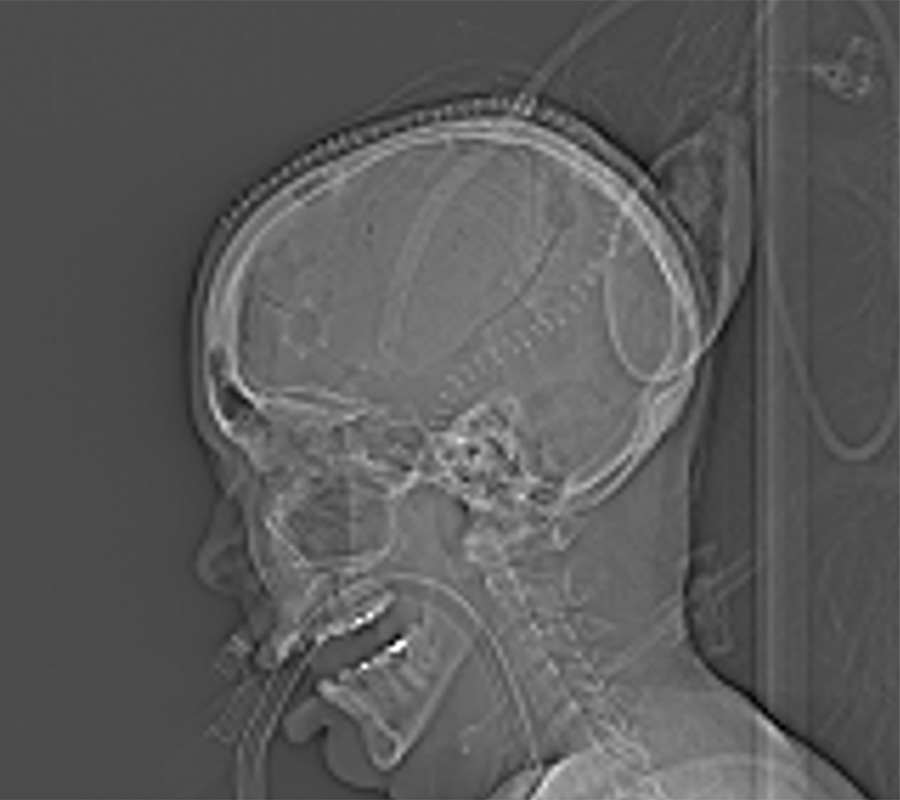

An ambulance was riding behind Davison and was able to quickly get her to the hospital. At the UAB Hospital Emergency Department, physicians from the UAB Division of Trauma and Acute Care Surgery evaluated Davison and sent her for a CT scan. They found a subdural hematoma — a collection of blood that forms between the brain and the outer layer of the brain’s protective covering — and subarachnoid hemorrhage, blood between the folds of the brain. UAB neurosurgery was consulted, and Davison immediately went into emergency brain surgery.

Davison had suffered a traumatic brain injury. She had a blood clot on the surface of the brain known as a subdural hematoma, evidence of bleeding in the brain, as well a few facial fractures. The blood clot caused pressure on the right side of her brain. The pressure needed to be relieved immediately to prevent worsening pressure on the brain, which can cause stroke, brain stem herniation, comatose, low respiratory function or even death.

In the OR, Riley performed a craniotomy and temporarily removed a bone flap from the side of the skull. She suctioned the blood clot and relieved the pressure in the brain. After the pressure was relieved, she secured the bone flap back onto the skull.

Davison suffered a traumatic brain injury. She had a blood clot on the surface of the brain. Her neurosurgeon performed a craniotomy to remove the clot and relieve pressure in the brain. “We felt really good about her prognosis and recovery,” Riley said. “Fortunately, Mrs. Davison was wearing a helmet during her accident. Her course could have been entirely different and potentially fatal had she not been wearing her helmet. It has been very exciting to see her make a good recovery.”